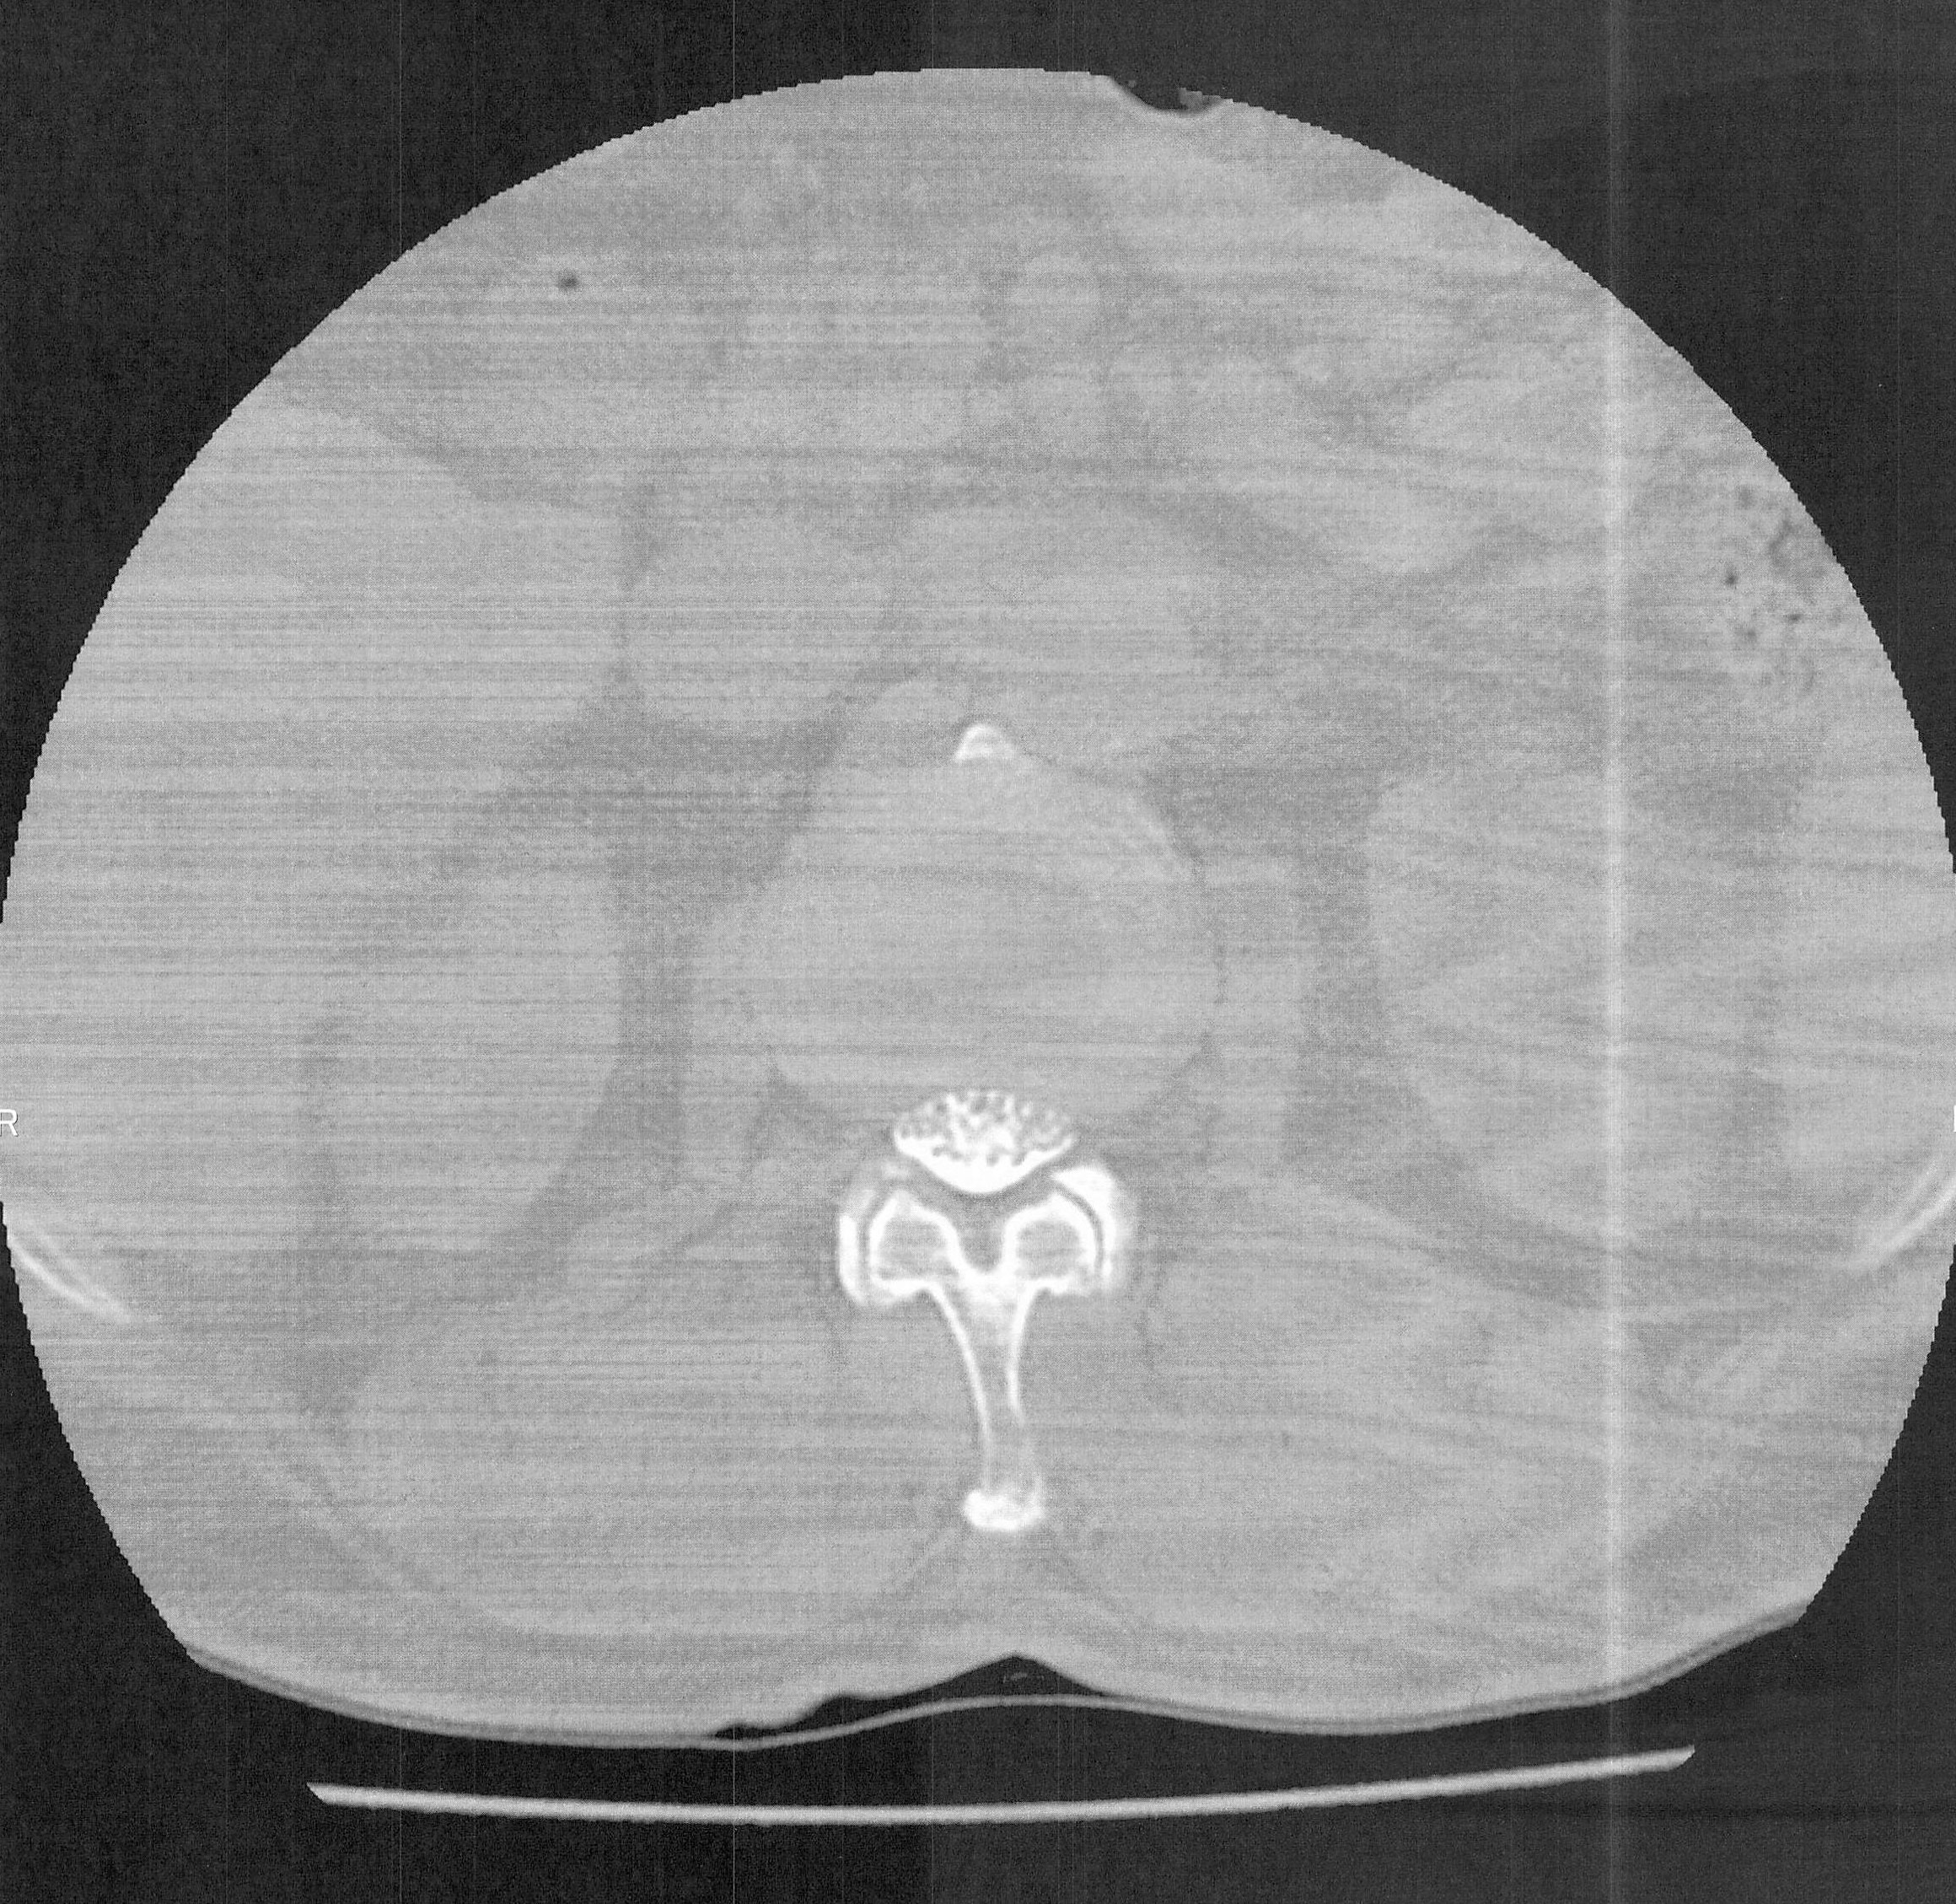

造影剤注入レントゲン検査の結果の画像は③の通りで、2か所の脊柱で造影剤が下に流れていないため、写つていないとのことで、ここで脊柱

管が特に狭窄状態をおこしているとの説明を受ける。